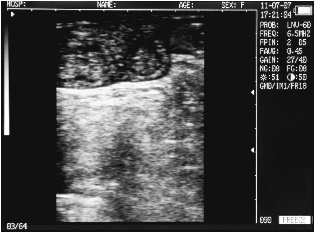

Uterine horn heifers